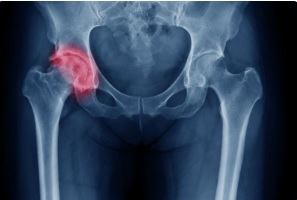

Перелом шейки бедренной кости — серьезное повреждение тазовых костей, которое может затрагивать как саму шейку, так и головку бедра, а также большой вертел. В отличие от остальных видов переломов в тазобедренной области, которые обычно срастаются, шейка бедра восстанавливается очень плохо, так как у неё другая анатомия кровоснабжения. После травмы кровь практически не поступает в зону перелома. Кроме того, нарушается питание головки бедра, развивается асептический некроз или коксартроз.